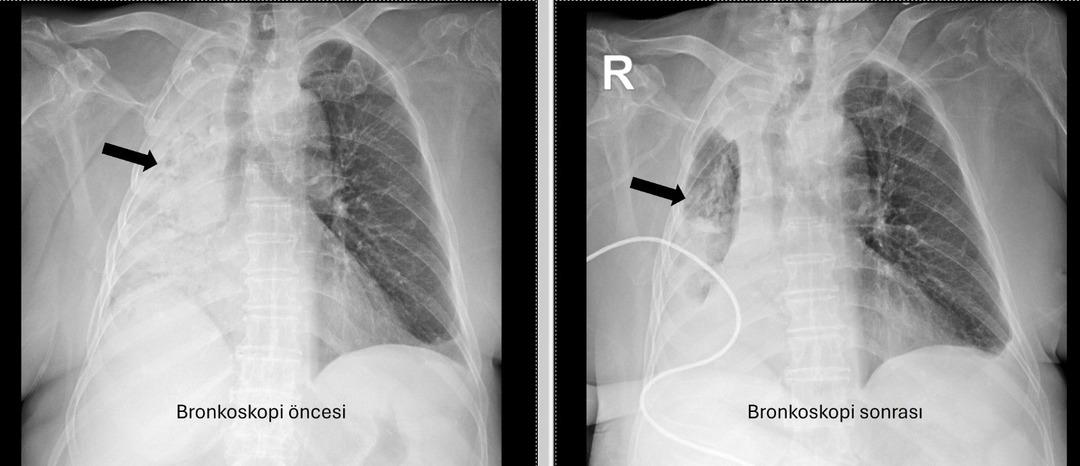

Yediği yemek az kalsın hayatından ediyordu: Sağ akciğeri tamamen kapandı! Soluk borusunu tıkadığı 5 ay sonra ortaya çıktı…

Denizli'de yaşayan 78 yıllık kadın ve emekli bir öğretmen yakın zamanda akciğer enfeksiyonu nedeniyle hastanede idi. 1 ay önce gittiği hastanede bronkoskopinin yapılmasına rağmen, sorunun tespit edilmediği öğrenildi. Yaşlı kadın, sağ akciğerin Pamukkale Üniversite Hastanesi'nin belirlenmesine tamamen kapatıldığı hastaneye gitti.

Pau Ökr Hastaneleri Göğüs Hastalıkları Bölümü. Prof.dr. Üye Dr.Köksel Altōiş Ergur, sağ akciğerler tarafından yapılan sınavlar için tamamen kapatıldı. Acil bronkoskopi planlandı ve prosedür derhal gerçekleştirildi. Dr. Al yaşşık ergur, hava yollarını incelerken çok yoğun ve karanlık bir salgılama ile esnek bir “bronkoskop” (esnek, katlanabilir), ancak hava yollarının derinlemesine temizlenmesini takiben, bir olaydan dolayı dönüştürüldüğünün, beraberinde bir şekilde dönüştürüldüğü ve beraberinde, bir olaydan dolayı dönüştürüldüğünü, berrak olduğunu, berrak olduğunu, berrak olduğunu açıkladığını, beraberinde kefil olduğunu açıkladığını açıkladığını açıkladığını açıkladığını açıkladığını açıkladığını açıkladığını açıkladığını açıkladığını açıkladığını, beraberinde getirdiğini açıkladığını açıkladığını açıkladığını açıkladı. Vücudun açık olduğu açık olduğu açık olduğu açık olduğu açıktı. genel anestezi ile yapılmıştır;

Prof. Alküzek Ergur, hastanın trakeasının nasıl engellendiğini açıkladı: “Havayollarında sıvı emen aspiratörün gücünü kullanarak nesneyi çıkarmak mümkün oldu. Hastanın hastanın tekrar yediği pizzada yediği pizza için daha önemli olduğu öğrenildi.